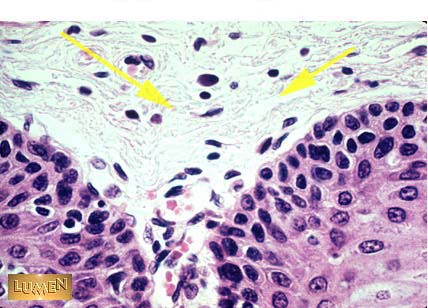

Loose Irregular Connective Tissue (Areolar Tissue)